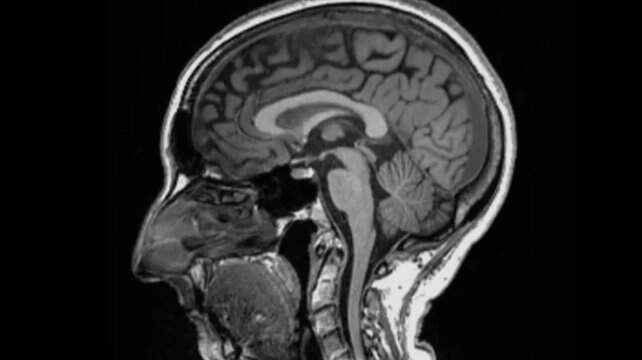

Pegar covid pode causar alterações no cérebro, sugere um estudo publicado na revista científica Nature. Cientistas encontraram diferenças significativas em exames de ressonância magnética realizados em pacientes antes e depois da infecção.

Mesmo após uma infecção leve, o tamanho geral do cérebro havia encolhido um pouco, com menos massa cinzenta nas partes relacionadas ao olfato e à memória. Os pesquisadores não sabem ainda se as mudanças são permanentes, mas enfatizaram que o cérebro é capaz de se recuperar.

– O tamanho geral do cérebro em participantes infectados havia encolhido entre 0,2 e 2%;

– Houve perdas de massa cinzenta nas áreas olfativas e regiões ligadas à memória;